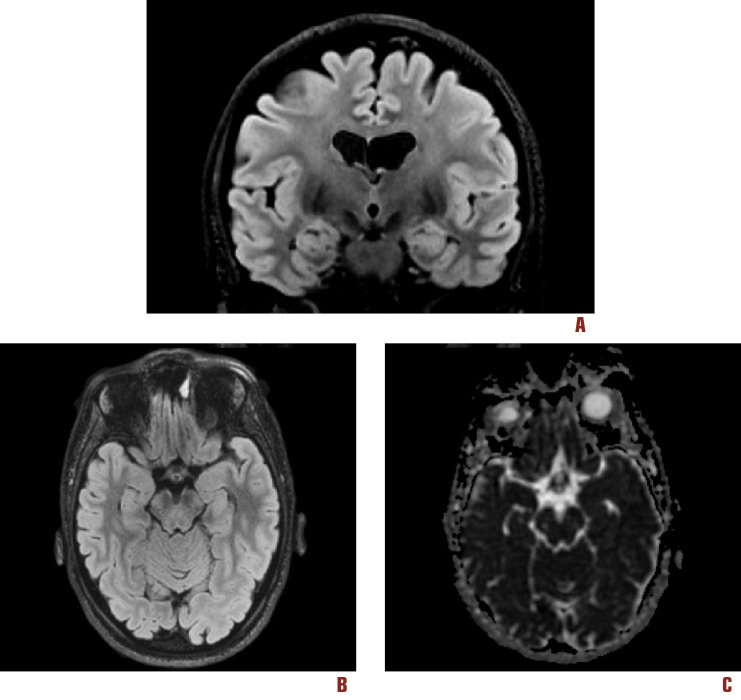

Dato che un motivo di sospensione della oxcarbazepina era stata un’eccessiva sonnolenza, come nuova terapia è stato impostato levetiracetam 1500 mg/die e si è ottenuta ancora completa remissione delle crisi. È stato eseguito inoltre controllo RM con magnete a 3T, in cui non sono risultate documentabili chiare alterazioni di segnale a carico delle strutture temporo-mesiali, salvo una residua lieve asimmetria per sinistra < destra; persisteva inoltre l’assenza di anomalie della mappa ADC (Figura 3).

Figura 3. RM – 3T di Follow-up. (A) Scansione T2 – FLAIR (Processed Images) coronale, (B) T2 – FLAIR assiale (Processed Images) e (C) mappa ADC. Alla RM 3T di follow-up sono scomparse le alterazioni di segnale a carico delle strutture temporo-mesiali, salvo una residua lieve asimmetria. Permane inoltre l’assenza di anomalie a carico della mappa ADC